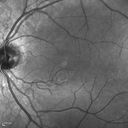

16 year old with incidental finding of retinal AV malformation but vision in the left eye is not as good as the right eye. VA OD: sc20/16 NscJ1+ VA OS: sc20/20-1 NscJ1+